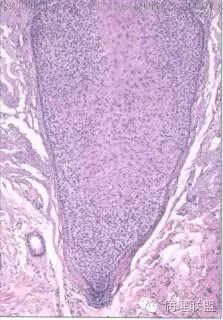

部位表浅,境界较为清楚,伴有不全角化;病变与表皮相连,由浅染细胞构成,周边细胞栅栏状排列;毛囊周边上皮环抱状改变;细胞无异型,核分裂看不太清(就知道这么一丢丢)@左淑英

@刘香丽 后面会有总结的,先看看书,记忆更好,外毛根鞘瘤:低倍看内生性生长,淡染或透明的鳞状细胞构成,边缘栅栏状排列的基地样细胞,外有嗜伊红地基底膜样物质。